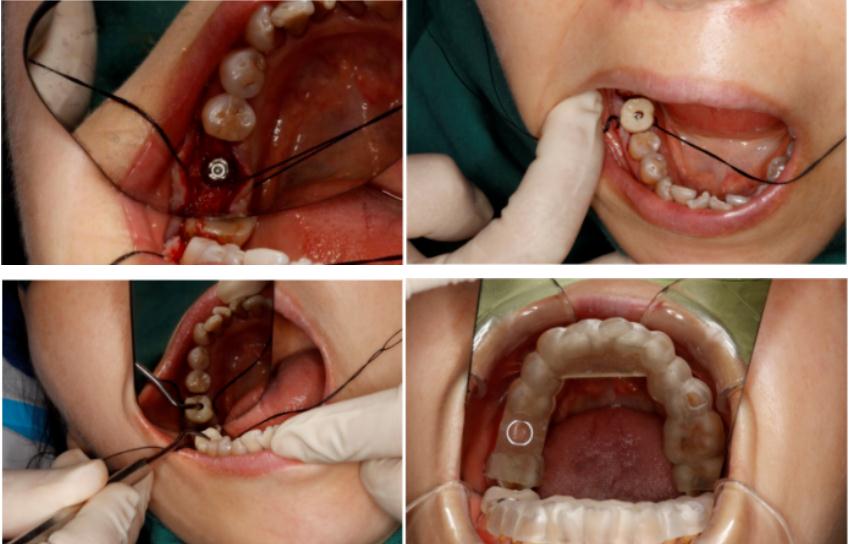

ng28南宫口腔类3D打印机打印的种植导板,配合精瓷义齿FC提供的专用手术工具盒,能够实现精准种植。根据以往数据整合,种植体实际植入的牙槽骨内位置,与术前设计规划的位置偏差小于等于1.2mm。在高精度的手术导板引导下在种植体植入的同时可以带入种植临时基台与临时修复义齿。

(医生在患者口内试戴种植导板并准备开始进行种植手术)

在精瓷义齿总经理钱总看来,在ng28南宫3D打印技术的帮助下,精瓷义齿FC种植平台完全数字化,为诊所医生与患者提供了一站式种植解决方案。对于医生来说可以医生可以在供应链上完成种植导板、种植配件、方案沟通确认等工作,对于患者来说可实现种植当天一日戴牙的诊疗效果,这种和谐的场面也是科技带来的必然结果。